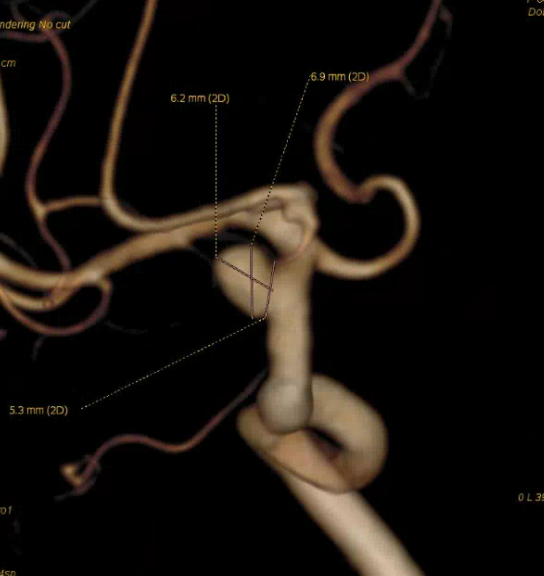

4mm×30mm Streamline

脑血管造影提示右侧颈内动脉颅内段多发动脉瘤(反主动脉弓)

脑血管造影提示右侧颈内动脉颅内段多发动脉瘤